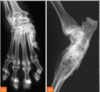

identify

Erosive polyarthropathy (rheumatoid arthritis) image of a dog

Feline digit-lung syndrome Primary neoplasia in lungs that causes Lytic changes in digital bones. We dont know why this happens in cats.

91